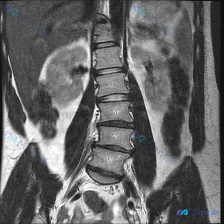

整理到一份影像资料,有点意思: 这是一张腹部MRI冠状位T2加权像,有人看了之后觉得存在脊柱侧弯,但放射科的正式报告里写的是「腰椎序列整体尚可」,还特意提了两侧腰大肌对称、双侧肾脏位置大致对称、没有明显的单侧病变导致的器官推移或结构扭曲。 实质性器官(肝、脾、肾)里也没见明确肿块、囊肿或异常高信号,...